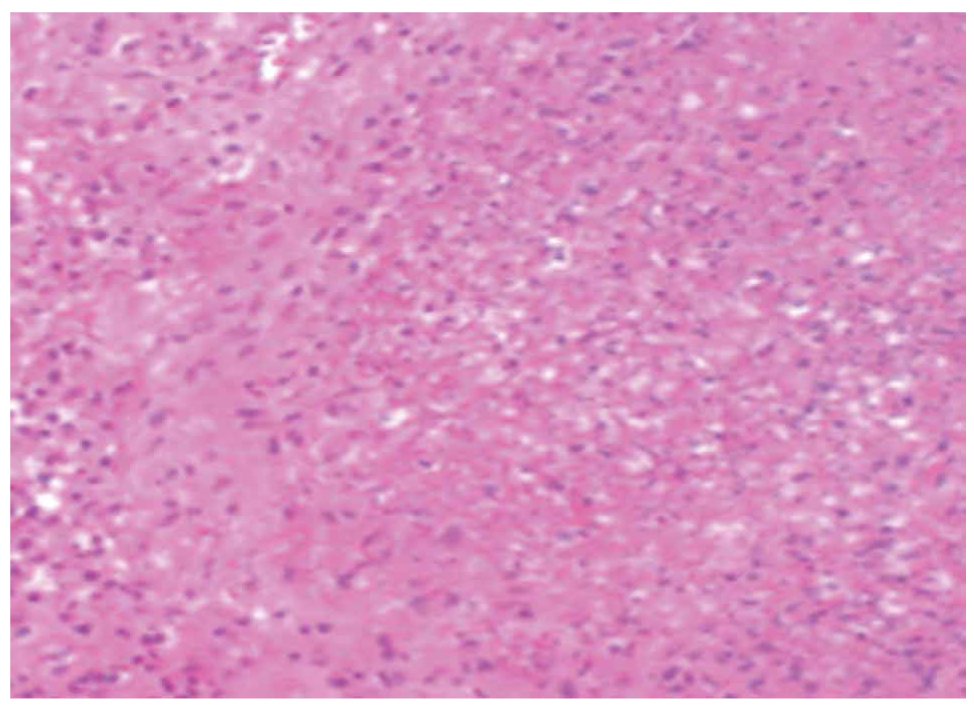

Two main histological subtypes exist: necrotizing and non-necrotizing granulomas [4]. Necrotizing granulomas have a necrotic focus surrounded by a rim of chronic inflammatory cells, including epithelioid macrophages [5] (Figure 1, 2). Although it is not a specific pathological finding, histologic identification of granulomatous inflammation is a useful predictor of diagnostic etiology and can lead to a definitive diagnosis with the aid of ancillary testing, such as special stains and molecular diagnostics. This is because the specific histologic patterns of the granuloma (e.g., foreign-body, necrotizing, non-necrotizing, suppurative, etc.) can help narrow the clinical differential diagnosis when considered alongside the clinical context (Figure 3, 4).

Figure 1. A 67-year-old patient with necrotic granulomatous lymphadenitis (x100).

Figure 2. Necrotic areas surrounded by a rim of epithelioid histiocytes and lymphocytes in the sample of the lymph node (x200).